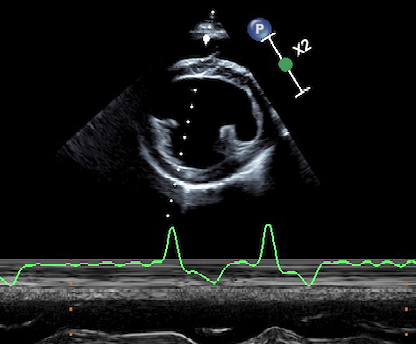

{{/_source.additionalInfo}}Nel cuore di riconosce uno specifico sistema di conduzione deputato a generare e condurre l’impulso elettrico al miocardio di lavoro. Tale sistema si compone di cellule in grado di generare l’impulso elettrico in maniera spontanea e di strutture rappresentate da fasci che propagano lo stimolo agli atri ed ai ventricoli. L’impulso elettric...